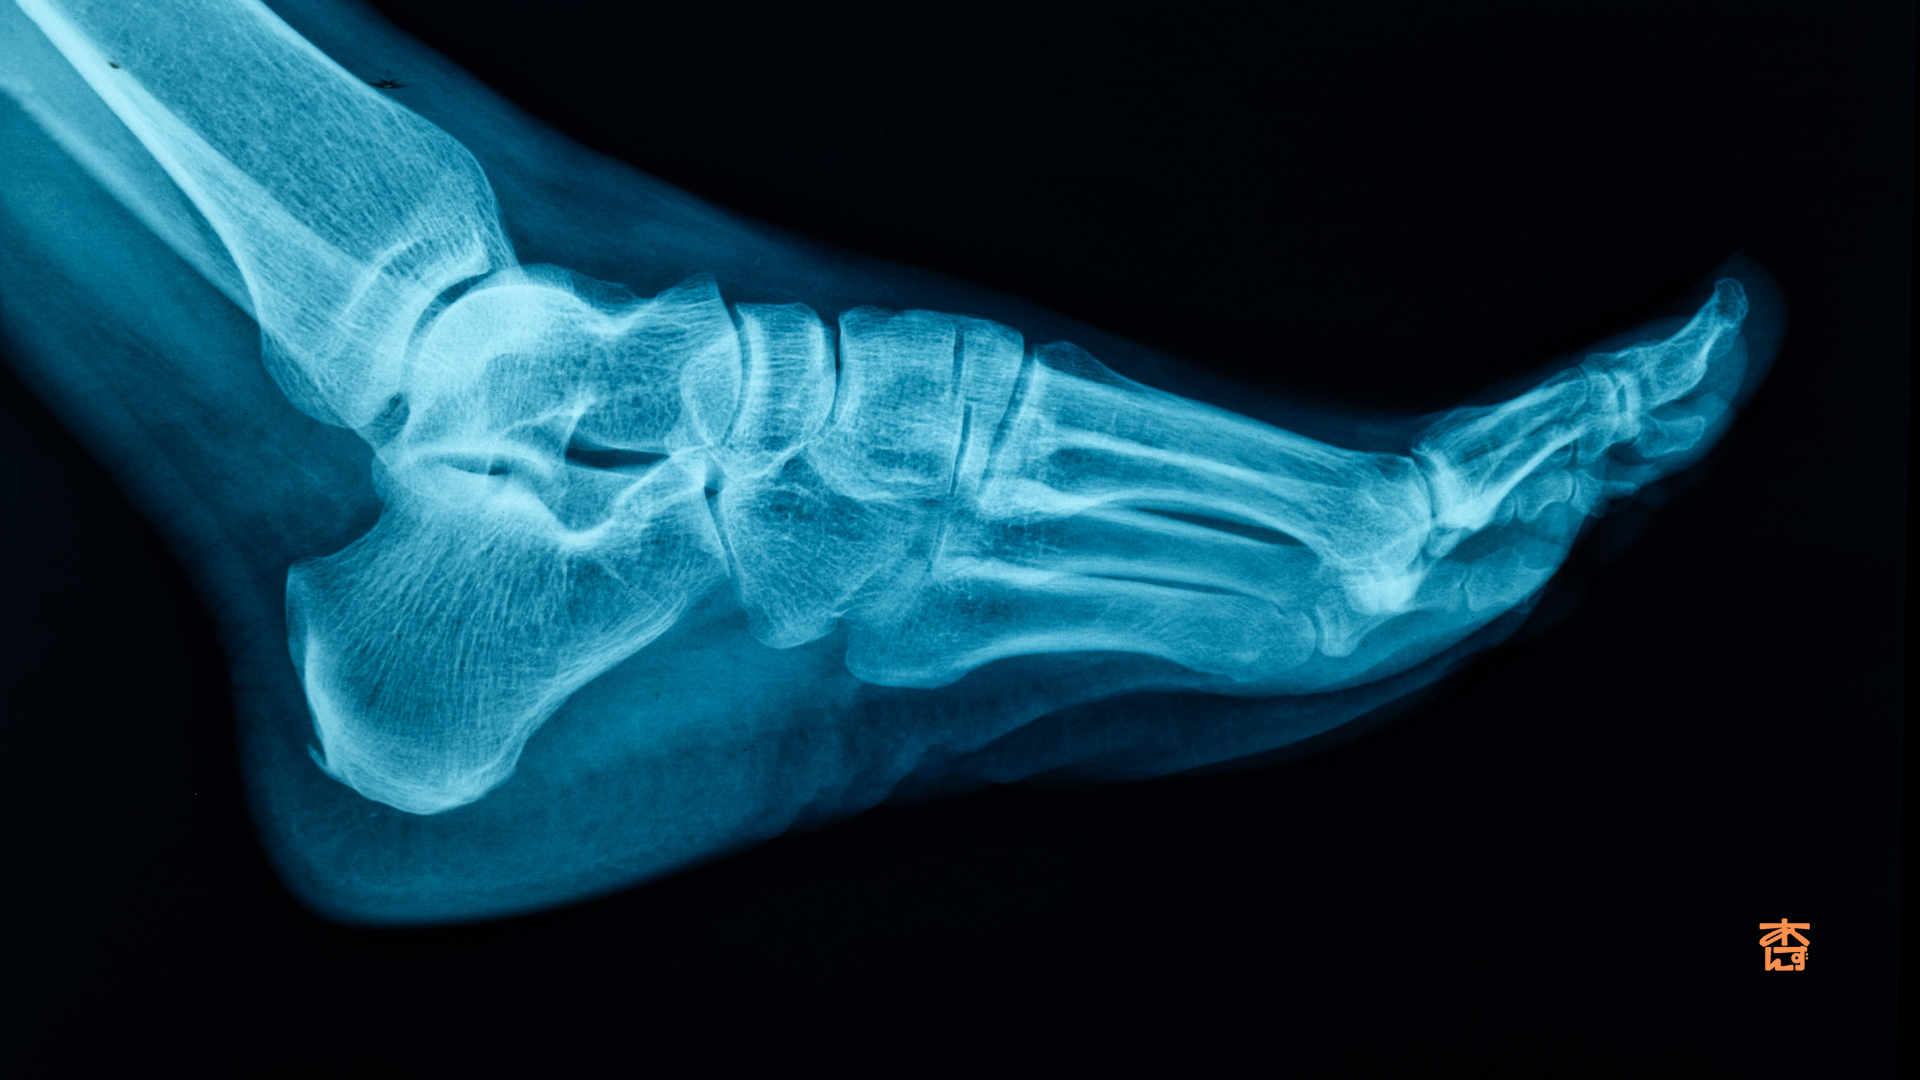

今回は腓骨下端骨折の記事です。

腓骨下端骨折とは?

腓骨ってどこの骨?

腓骨はすねにある二本の骨のうち外側(小指側)にある細い骨のことです。

足首に近い部分(下端)は特に骨折しやすい場所として知られています。

転倒したときや足首を強くひねったときなどに折れてしまうことが多いんですね。

特にスポーツをされる方や高齢の方に多く見られる骨折です。

まず、レントゲン検査などで骨折の状態を確認します。その上でLIPUSによる治療が適切かどうかを医師が判断します。